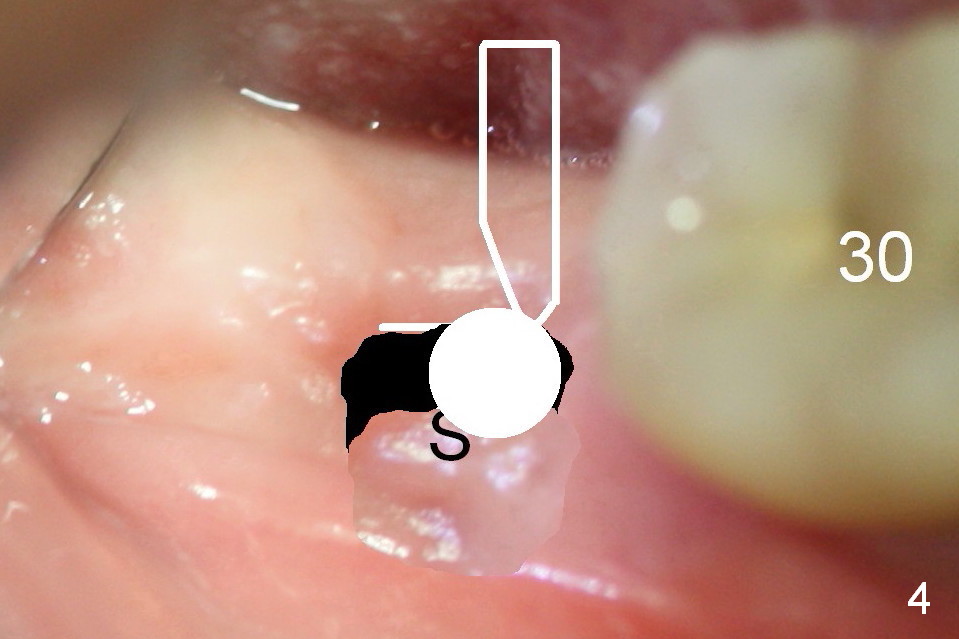

Steps of Bone Expansion (Illustration)

After incision and flap elevation, use #15 blade (Fig.1 white outline) to start bone expansion as lingual as possible (white line). Use bone scalpels, bone blades and D osteotomes to push the bone buccally (Fig.2 arrow). Use 2 mm pilot drill to initiate osteotomy as lingual and mesial as possible (Fig.3 white circle). The next step is to use bone expanders as apical as possible (Fig.4 white circle). If the apical bone is hard, use drills at 50 RPM (to collect bone).